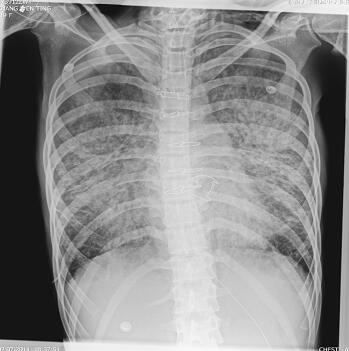

第二阶段(入院后第7~26天):二尖瓣置换术后患者心功能明显改善,多次复查心脏超声均提示心脏舒张及收缩功能未见明显异常,瓣膜功能良好。但患者感染难以控制,考虑感染源:①肺部感染:无法脱离ECMO,胸片提示双肺渗出影(图1),多次痰培养结果均提示鲍曼不动杆菌(MDR);②血源性感染:多次外周血及导管血培养提示洋葱伯克霍尔德菌;③感染性心内膜炎:考虑患者存在急性感染性心内膜炎,瓣膜赘生物形成,多为革兰阳性杆菌感染,但赘生物培养却未见细菌生长。鉴于以上感染相关证据,调整抗感染治疗方案为达托霉素和美罗培南联合左氧氟沙星,并加强气道管理,入院24天后病情明显好转,感染得到控制,逐渐增加呼吸机支持条件,并降低ECMO辅助条件,患者氧合及循环情况均未见恶化,复查胸片渗出较前吸收(图2~图4),故入院后第26天脱离ECMO,在常规机械通气的情况下,患者指脉氧饱和度可维持在95%左右,监测乳酸在1.0mmol/L左右,经皮氧分压88mmHg,经皮二氧化碳分压50mmHg。

图3 ECMO撤离前

图4 ECMO撤离后